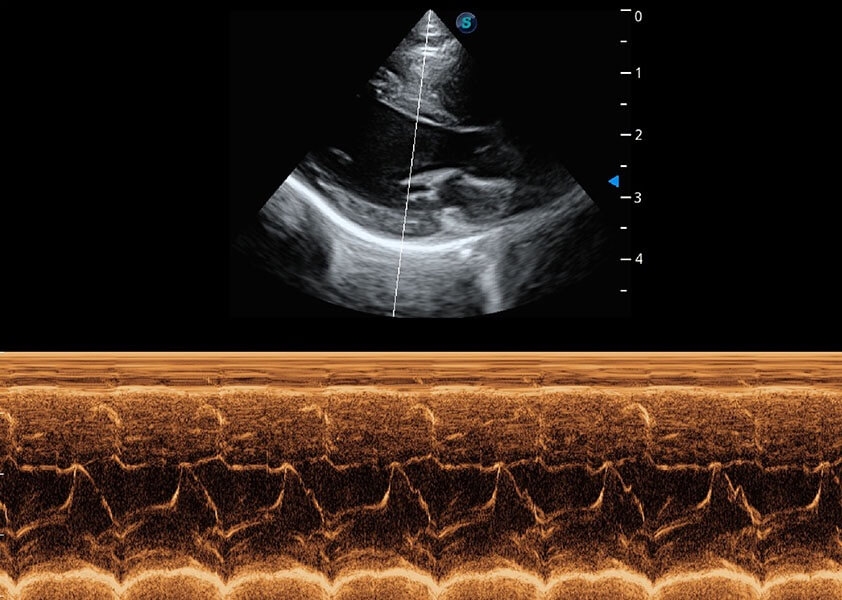

ProPet 60 作为一款高端台式动物超声设备,为动物医生的日常诊断提供了一系列贴合动物临床需求、解决临床实际问题的高级成像功能。凭借全系列高清探头,满足医生对腹部、心脏、生殖、浅表、肌骨等成像的所有需求,切实帮助您提升检查效率,提高诊断信心。

动物是人类最亲密的朋友和最值得信赖的伙伴。竞技宝(JJB)官方网站也一直致力于探索动物专用的超声影像解决方案。 全新推出的ProPet系列,是竞技宝(JJB)官方网站在动物超声影像智能化、专业化、精准化的一次跨越式革新。动物不能用言语来表述自己的不适,通过超声影像,ProPet系列搭建了动物医生与不同物种沟通的“桥梁”,为动物医生注入了“治愈之力”。